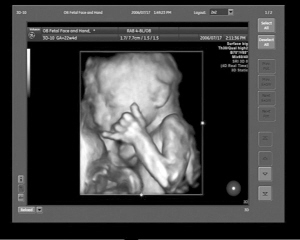

英国《镜报》日前报道,一个用户名为“Meancloth”的网友在社交网站Reddit上传了一张妻子的B超照片,显示了子宫中胎儿竖大拇指的样子,似乎在赞扬父母为其创造了不错的居住环境。

“宝宝在妈妈肚子里本来就是很活泼的。”杭州艾玛妇产医院执行院长朱春芝说,B超室里经常能看到各种萌态的胎宝宝,跷着二郎腿的、托腮嘟嘴的、吃手指解馋的,宝宝们玩耍得很愉快,可都没闲着。